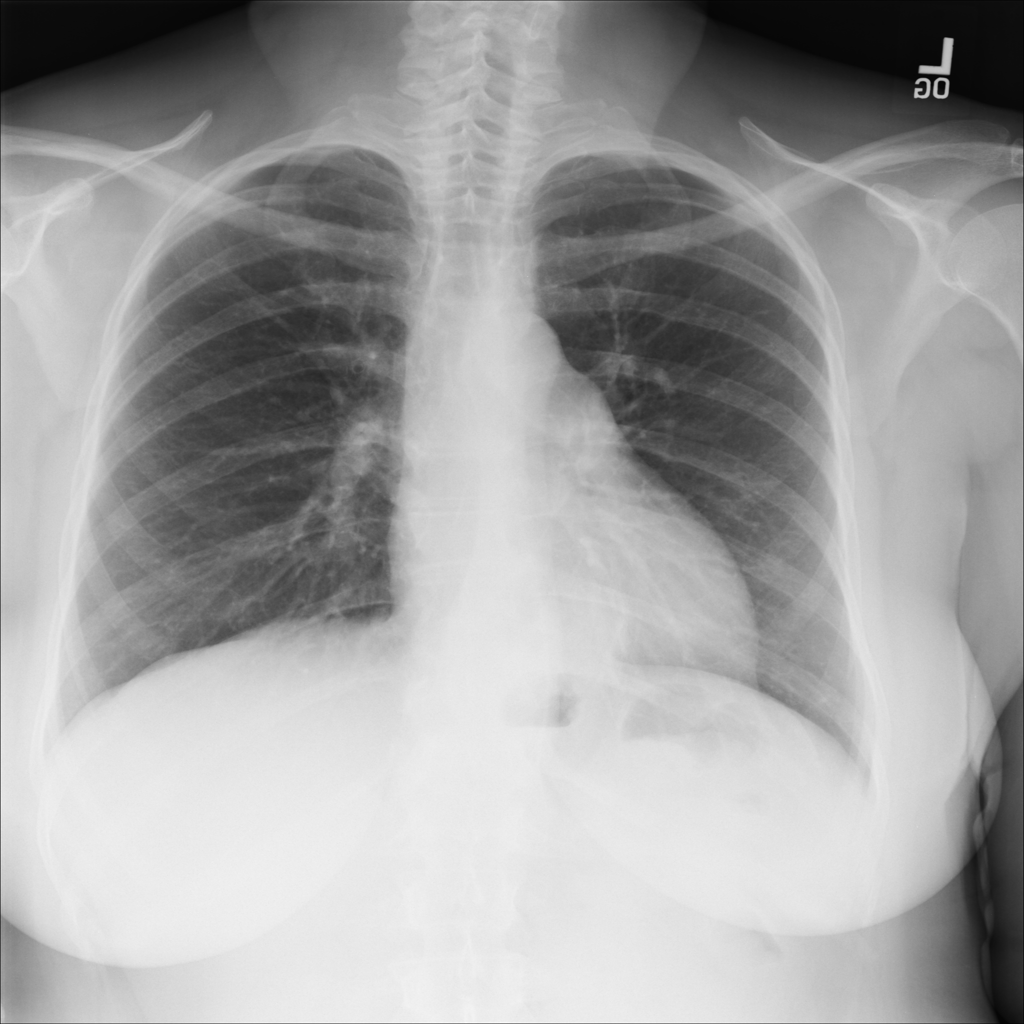

PAT-C048 · IMG-001Hernia

PAT-C048 · IMG-001

PA